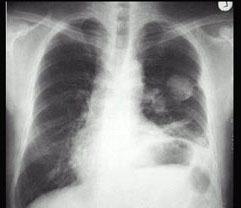

问题 男,67岁,胸痛半月,胸片检查如图,最可能的诊断为 ( )

选项 A、左上肺球形不张 B、左上肺脓肿 C、左上肺周围型肺癌 D、左上肺炎性假瘤 E、左上肺结核球

答案 C